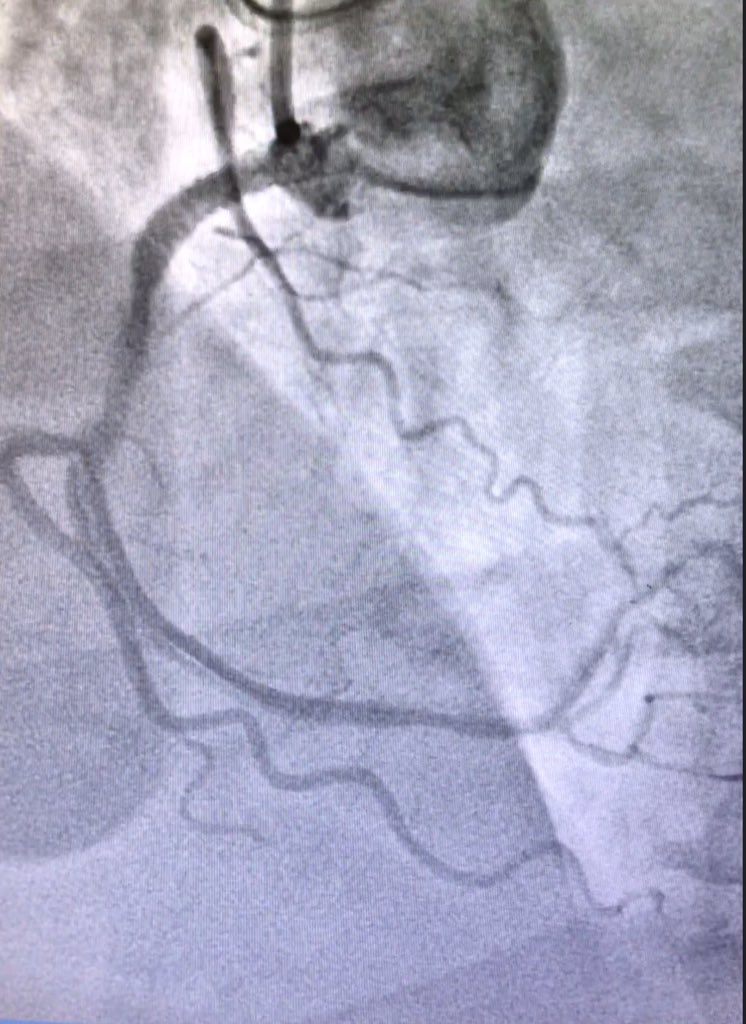

Uh oh what next #CTO101 Robert W. Yeh Hector Tamez, MD MPH jcspratt

Robert W. Yeh Hector Tamez, MD MPH jcspratt 1. Check pt-fine 2. Check diaper- unsoiled for now. 3. No more injections and change to JR4. Don't need Al support 99% of time R to L.

Robert W. Yeh Hector Tamez, MD MPH jcspratt Wired LAD stented and went retro into rca. See stain. Miraculously stable. Would star if unstable.

Robert W. Yeh Hector Tamez, MD MPH jcspratt Snared, externalized, in control, what next?